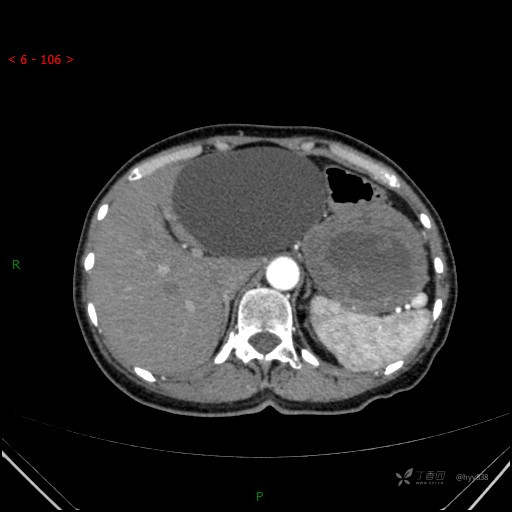

增强静脉期